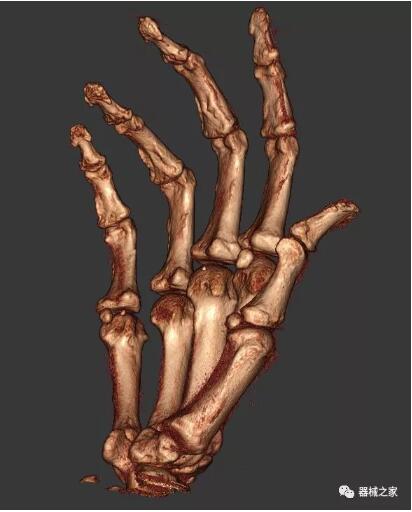

另外一款被稱為世界上最小的CT,它的重量僅300磅,不僅能夠掃查足部,還可以檢查膝蓋和上肢等。

與上面介紹的CT一樣,它同樣具有輻射低、占地空間?。?3*36)的特點,隨開隨用(支持直接接入墻上的插座)。

這款CT使用非常方便,通過上下移動保持與患者的手臂或者雙腿齊平,掃描快速,僅需要30秒左右就可以完成掃查。

以上介紹的CT均來自國外同一家公司,這些CT均配置了可視化軟件,可以進行切片、3D重建以及大型CT附帶的所有典型的操作功能。

以下是這些“特立獨行”的CT所拍出來的圖像: